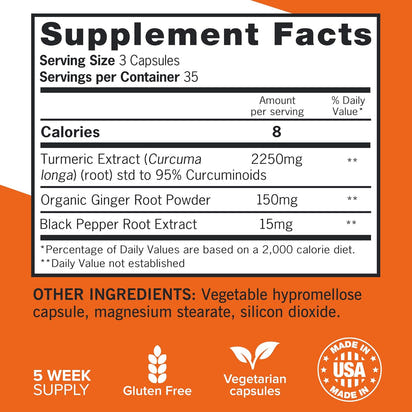

Unlock your potential with this powerful blend of turmeric, black pepper, and ginger, designed to support joint health and enhance your active lifestyle. Embrace vitality and comfort every day with our extra-strength formula.

- 2400mg turmeric extract per serving

- 95% curcuminoids for maximum benefits

- Enhanced absorption with black pepper

- Organic ginger root for soothing support

Answer 2: Black pepper extract significantly boosts the bioavailability of curcumin, allowing your body to absorb and utilize the active ingredients more effectively. This means you get the maximum benefits from each dose, ensuring your investment in joint support yields optimal results.